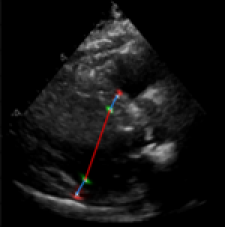

| (a) LV Measurements | (b) Label Smoothing |

Left Ventricular Hypertrophy (LVH), one of the leading predictors of adverse cardiovascular outcomes, is the condition where heart’s mass abnormally increases secondary to anatomical changes in the Left Ventricle (LV) [10]. These anatomical changes include an increase in the septal and LV wall thickness, and the enlargement of the LV chamber. More specifically, Inter-Ventricular Septal (IVS), LV Posterior Wall (LVPW) and LV Internal Diameter (LVID) are assessed to investigate LVH and the risk of heart failure [21]. As shown in Figure 1 (a), four landmarks on a parasternal long axis (PLAX) echo frame can characterize IVS, LVPW and LVID, and allow cardiac function assessment. To automate this, machine learning-based (ML) landmark detection methods have gained traction.